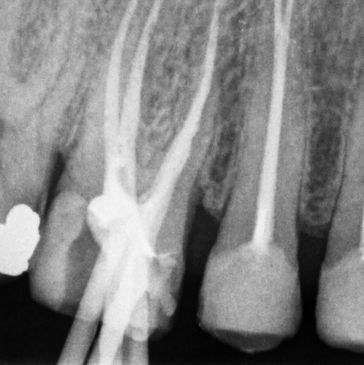

Kanal tedavisi tekrarı (Retreatment), en sadece basit tanımı ile kök kanalı içerisinde gerçekleştirilen eski tedavi ve dolgunun temizlenerek, yeniden kanal anatomisine uyumlu bir şekilde kanal tedavisinin gerçekleştirilmesidir.